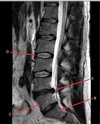

How well did you know this?

1

Not at all

2

3

4

5

Perfectly

Q

What is letter D?

A

SPINAL CORD